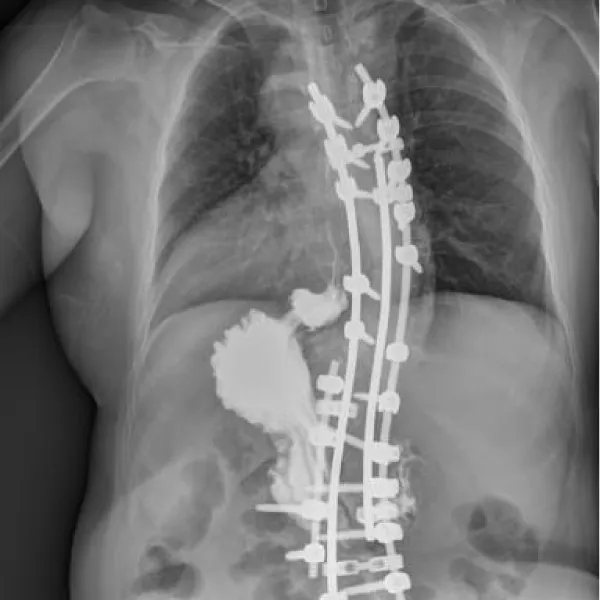

The patient had a history of spinal correction surgery for scoliosis five years ago, during which her SIT was identified. Our CT exam and gastrogram proved her history, with a hernia sac measuring 35*48 mm (Figures 2-4). All routine laboratory tests were within normal limits.

Download Image

Figure 2: Front view of the gastrogram before surgery.

Figure 3: Lateral view of the gastrogram before surgery.